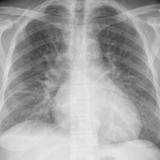

APE 4

Date: 11/05/2005

Views: 2939